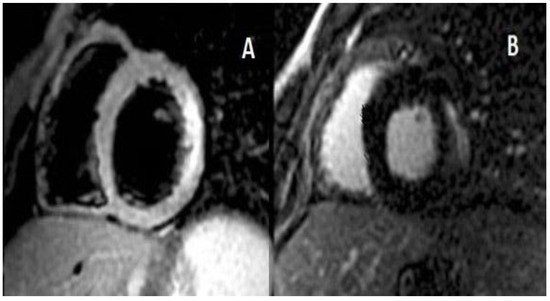

2. Case Report